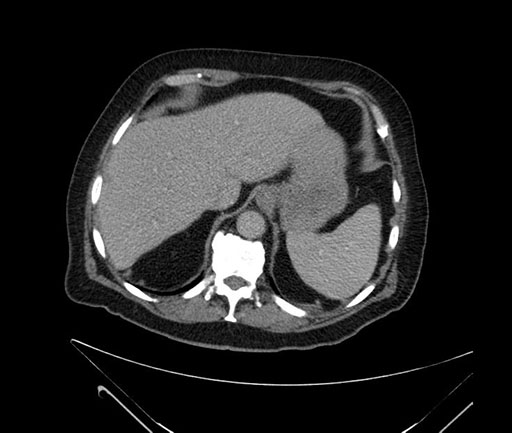

Whipple (pancreaticoduodenectomy) [case 7]

Imaging Analysis

Look through the patient's CT scan to identify any areas of concern for the necessary procedure.

Axial - stented